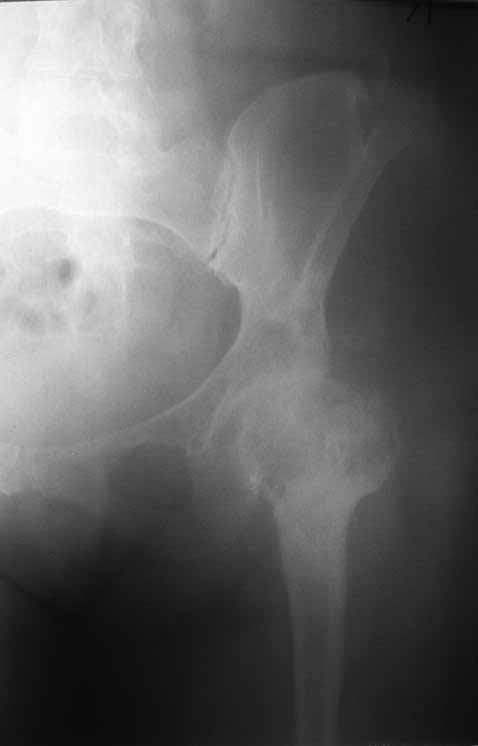

Уважаемые коллеги. Хотелось бы услышать мнения и советы по представляемому случаю.

месяцев удалил фиксаторы, а в 2009г. резецировал мениск на противоположной стороне. Боли

все эти годы не беспокоили. Пациентка чуть выше среднего роста, вес тела нормальный.

Физические нагрузки переносила хорошо. Работает на 7 этаже без лифта. Год назад экстирпация

матки по поводу лейомиомы больших размеров. Несколько месяцев назад появились боли в

области левого тазобедренного сустава. При рентгеновском и КТ исследованиях (июль с.г.)

нестабильность тазового компонента. От предложенной замены протеза пациентка на тот

момент, слава богу, отказалась. Через какое то время боли в области левого тазобедренного

сустава практически полностью прошли, а около 2 месяцев назад появилось ощущение

патологической подвижности таза и боли в паху справа, которые через некоторое время

уменьшились, а потом снова усилились после значительных физических нагрузок (много ходила

по песку на пляже, носила тяжести). Ежедневно принимала диклофенак. На рентгенограммах

переломы правой лонной кости. Сейчас госпитализирована из-за болей в паху справа. Боли

слева не беспокоят. На фоне снижения нагрузок в стационаре боли значимо уменьшились.

Способна ходить без средств дополнительной опоры. В анализах крови чуть повышены

трансаминазы и гамма-ГТ, моча без особенностей.

-Если думать о ревизии, то когда? На представленных снимках тазобедренный сустав до и

сразу после операции, затем 2 снимка 2009г., когда ничего не беспокоило, затем КТ 2-х

месячной давности и вчерашние рентгенограммы обоих тазобедренных суставов.